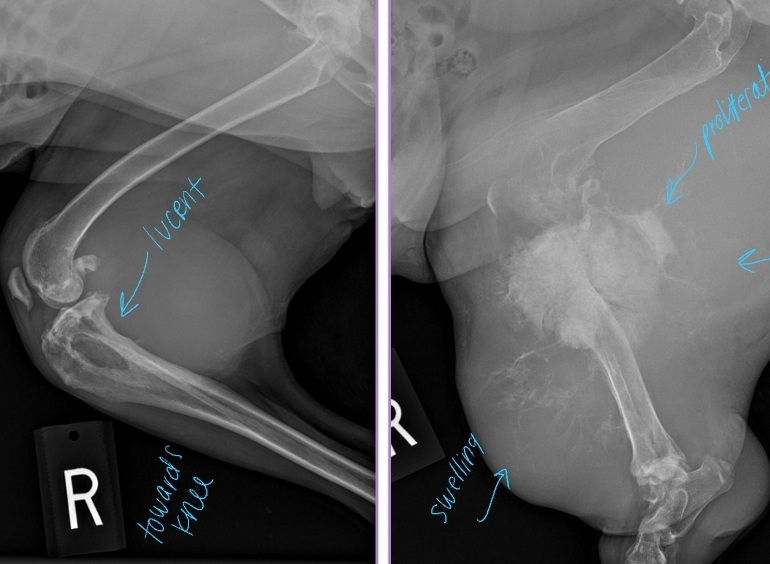

Primary Bone Neoplasia

Et: Osteosarcoma, Chondrosarcoma

Cs: Lameness, Muscle atrophy, Bone swelling

Dt: Radiographs #1, CT, Bone biopsy

Osteolysis, Osteoproliferation, Soft tissue swelling

“Away from the elbow, toward the knee”

proximal humerus, distal radius/ulna & distal femur, proximal tibia

Tx:

Amputation: Eliminates pain, MST 6 months

Amputation + Chemo: Eliminates pain, MST 12 months

Primary Stabilization + Chemo: Allows mobility, MST 12 months

Chemo adds extra time of survival!!